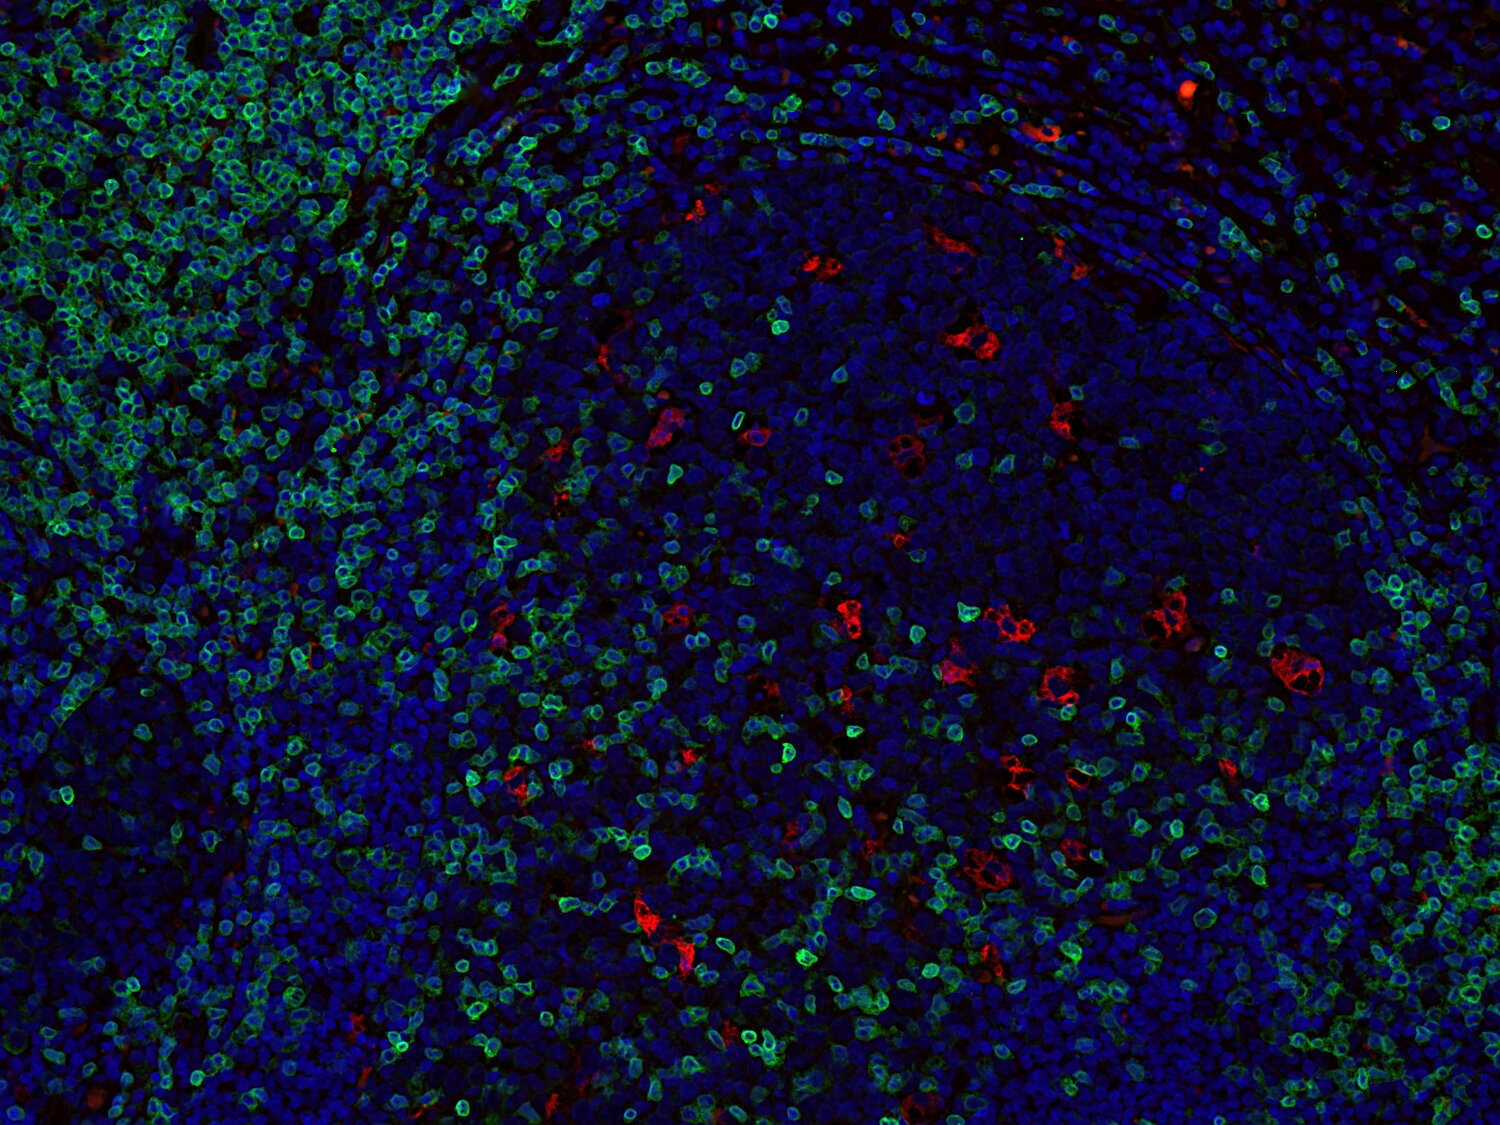

Immunofluorescence image of a human FFPE tonsil section stained for CD3e (T cells, green) and CD68 (macrophages, red)

Cluster of differentiation 3 (CD3) is a defining feature of cells belonging to the T cell lineage. It is composed of the four subunits CD3 gamma, CD3 delta, CD3 epsilon (CD3e) and CD3 zeta, that form a multimeric protein complex. This complex associates with the T cell receptor (TCR) and serves as a T cell co-receptor. The CD3 molecules contain immunoreceptor tyrosine-based activation motifs (ITAMs) that serve as the nucleating point for the intracellular signal transduction machinery upon TCR engagement. TCR/CD3 signaling is central to the initiation of antigen-specific T cell responses to pathogens and vaccines, as well as transplanted tissues, tumors, and autoantigens. CD3 is initially expressed in the cytoplasm of pro-thymocytes. During T cell maturation the expression of CD3 migrates to the cell-membrane. The specific appearance at all stages of T cell development make CD3 a useful immunohistochemical marker for T cells in tissue sections. In the clinical setting, CD3 is a relevant marker for the classification of malignant lymphomas and leukemias as the antigen remains present in almost all T-cell lymphomas and leukemias. It can also be used to detect T cells in celiac disease, lymphocytic and collagenous colitis.